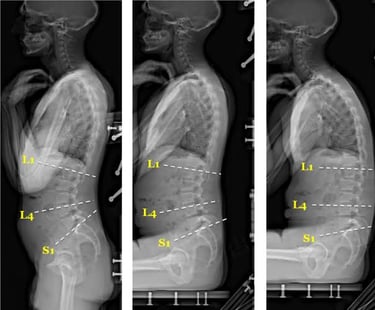

Best Chiropractic sciatica pain relief doctor in chennai tamilnadu for instant relief from sciatica back Pain, L4 L5 S1 disc buldge and degeneration problem and posture correction to solve recurring Pains.